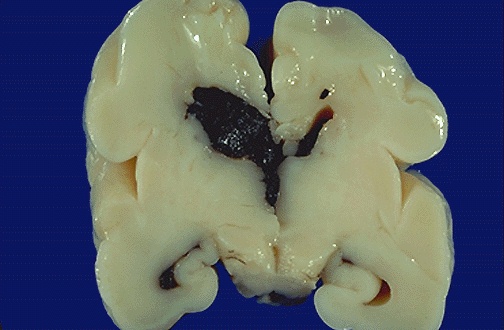

| This is intraventricular hemorrhage (IVH) which arose in the subependymal region (germinal matrix) of a 28 week gestational age newborn. The germinal matrix region is very susceptible to such lesions at this period of development, leading to IVH as a complication of prematurity. |